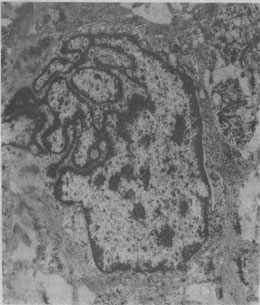

图1-1 恶性肿瘤细胞的奇异形核 图中央为一巨大的瘤细胞核,核膜曲折凹陷,使核呈奇异形(纤维肉瘤的电镜照片) ■[此处缺少一些内容]■ 5.核仁的改变 核仁(nucleolus)为核蛋白体RNA转录和转化的所在。除含蛋白的均质性基质外,电镜下核仁主由线团状或网状电子致密的核仁丝(nucleolonema)和网孔中无结构的低电子密度的无定形部(pars amorpha)组成。核仁无界膜,直接患浮于核浆内。 形态上和生物上核仁由3种不同的成分构成:①原纤维状成分,内含蛋白质及与其相结合的45S-rRNA;②细颗粒状成分,主要由12S-rRNA构成,为核仁的嗜碱性成分;③细丝状成分,仅由来自胞浆的蛋白质构成,穿插于整个核仁内。3种核仁成分的空间排列状态可反映细胞的蛋白合成活性,例如: 壳状核仁:原纤维状成分集中位于核仁中央,细颗状成分呈壳状包绕于外层。这种细胞的合成活性甚低。 海绵状核仁:这种核仁的原纤维状与细颗状成分呈海绵状(或线团状)排列。这种细胞的合成活性升高。大多数所谓的“工作核”具有这种核仁。 高颗粒性核仁:由海绵状核仁转化而成,原纤维状成分几乎消失,核仁主要由颗粒状成分构成,故组织学上呈强嗜碱性,细胞的合成活性旺盛。这种核仁常见于炎症和肿瘤细胞。 低颗粒性核仁,与上述高颗粒性核仁相反,这种核仁的细颗粒状成分锐减,故电镜下原纤维状成分显得突出,电子密度较低。这种核仁常见于再生时,因此时细颗粒成分(rRNA)过多地被胞浆所利用。 分离性核仁:超微结构上3种核仁成分清楚地互相分离,原纤维状和细颗粒状成分减少。这种核仁变小,无活性,常见于核仁转录过程被抗生素、细胞抑制剂、缺氧和蝇菌素中毒等所完全阻断时。 由此可见,核仁的大小和(或)数目的多少常反映细胞的功能活性状态:大和(或)多的核仁是细胞功能活性高的表现,反之则细胞功能活性低。